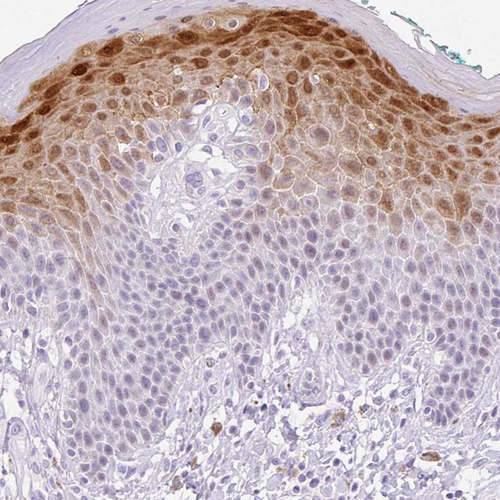

Immunohistochemical staining of human placenta shows no positivity in trophoblastic cells as expected.